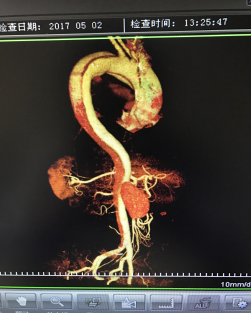

5月2號劉大伯照常早起干活,突然胸部劇烈疼痛,難以忍受,全身大汗,同時伴有右上肢發(fā)涼,他心想這次心絞痛比之前嚴(yán)重的多啊,趕緊叫上孩子到吉林國文醫(yī)院心血管內(nèi)科住院,患者長期高血壓病史,血壓一直控制不理想,大夫給他做了檢查,測左上肢血壓:82/45mmHg,右上肢血壓測不出,心率52次/分,右側(cè)肱動脈、尺動脈、橈動脈搏動消失,左側(cè)股動脈搏動較右側(cè)弱?!霸懔耍p側(cè)血壓差別這么大,是不是主動脈夾層了?”,接診大夫趕緊找來李主任,李主任反復(fù)詢問患者病情,表情突然凝重起來,患者胸痛這么明顯,血壓低的厲害,主動脈夾層的可能性很大。二話不說,李主任立即聯(lián)系影像科的醫(yī)生準(zhǔn)備做主動脈CTA,移動患者做檢查的過程大夫們非常小心,嚴(yán)密監(jiān)測患者血壓變化情況。兩個小時后結(jié)果出來了,主動脈夾層從升主動脈一直撕裂到左側(cè)髂總動脈?。?!

從開始學(xué)醫(yī)到現(xiàn)在已經(jīng)快9年了,主動脈夾層患者也見過一些,但像劉大伯這種危險類型的還是第一次見到,心里真的為他捏把汗,撕裂的主動脈隨時都有可能破裂,生命隨時可能終止,要知道主動脈夾層的死亡率非常的高,約50%的患者發(fā)病后48小時死亡,約90%的患者發(fā)病1個月內(nèi)死亡。